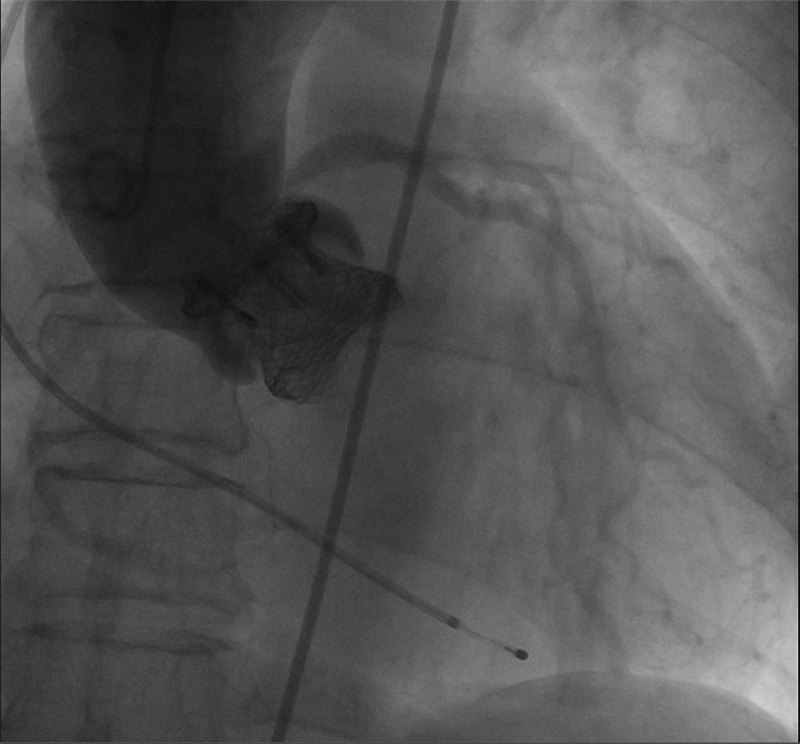

2 结果两例患者手术均顺利进行,第一例患者瓣膜一次释放成功,术后无瓣周漏(见图 2);第二例患者第一次释放位置欠佳,重新回收后再次释放,术后少量瓣周漏;均未出现死亡、脑卒中、冠脉堵塞、心包填塞等并发症;第一例患者术后出现了完全性左束支传到阻滞,但无相关症状未植入起搏器,第二例患者未出现新发生的传导阻滞。

|

| 图 2 Lotus瓣膜置入后造影图像 Fig 2 Image after transcatheter Lotus aortic valve replacement |

出院前两例患者的症状较术前明显好转,AVA分别提高到1.56 cm2和1.68 cm2,Vmax分别下降到2.87 m/s和2.76 m/s,PGmean分别下降到18 mmHg和15 mmHg。术后30 d随访提示:纽约心功能分级均改善到Ⅱ级,AVA分别为1.67 cm2和1.91 cm2,Vmax分别为2.5 m/s和2.65 m/s,PGmean均为14 mmHg,较出院时有进一步的改善,瓣周漏与术后即刻一致,分别为无瓣周漏和少量瓣周漏,远期疗效有待于进一步随访。